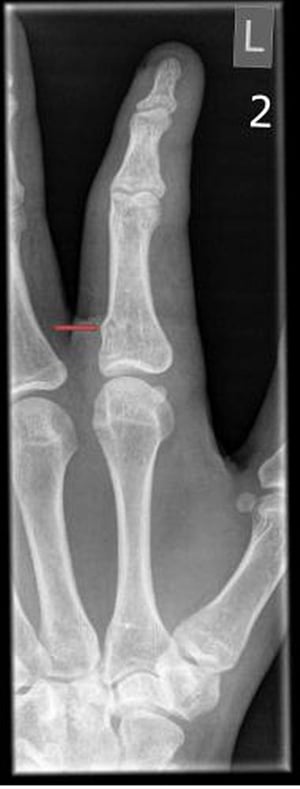

Компресійний веретеноподібний перелом кісток пальця

Компресійний веретеноподібний перелом може візіалізуватися лише у вигляді дрібних нерівностей кіркового кісткового шару.

Компресійний веретеноподібний перелом може візіалізуватися лише у вигляді дрібних нерівностей кіркового кісткового шару

PHOTOSTOCK-ISRAEL/НАУКОВА ФОТОБІБЛІОТЕКА